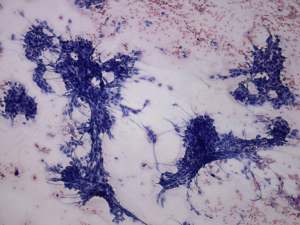

Cytological diagnosis: anaplastic carcinoma.

Histopathology: anaplastic carcinoma.